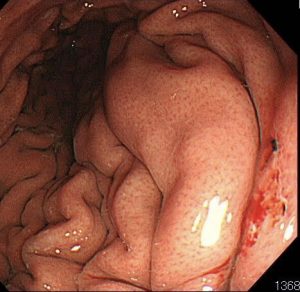

赤く盛り上がった部分が、実は「早期胃がん」です。胃がんにアニサキスが食いついていました。